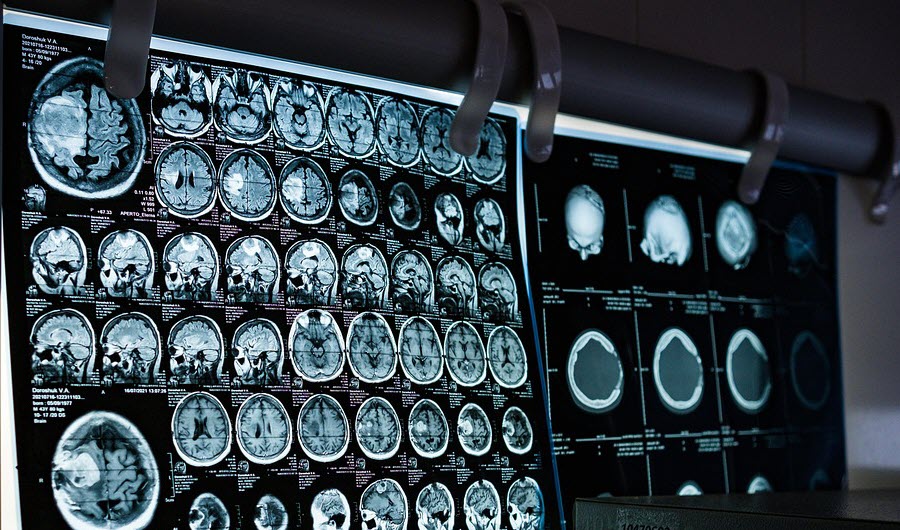

What is a Concussion?

A concussion is a form of traumatic brain injury caused by a bump, blow, or jolt that causes the head and brain to move back and forth rapidly. It is possible to have a concussion due to whiplash, or rapid rotation, shaking or jerking of the head or even the body.